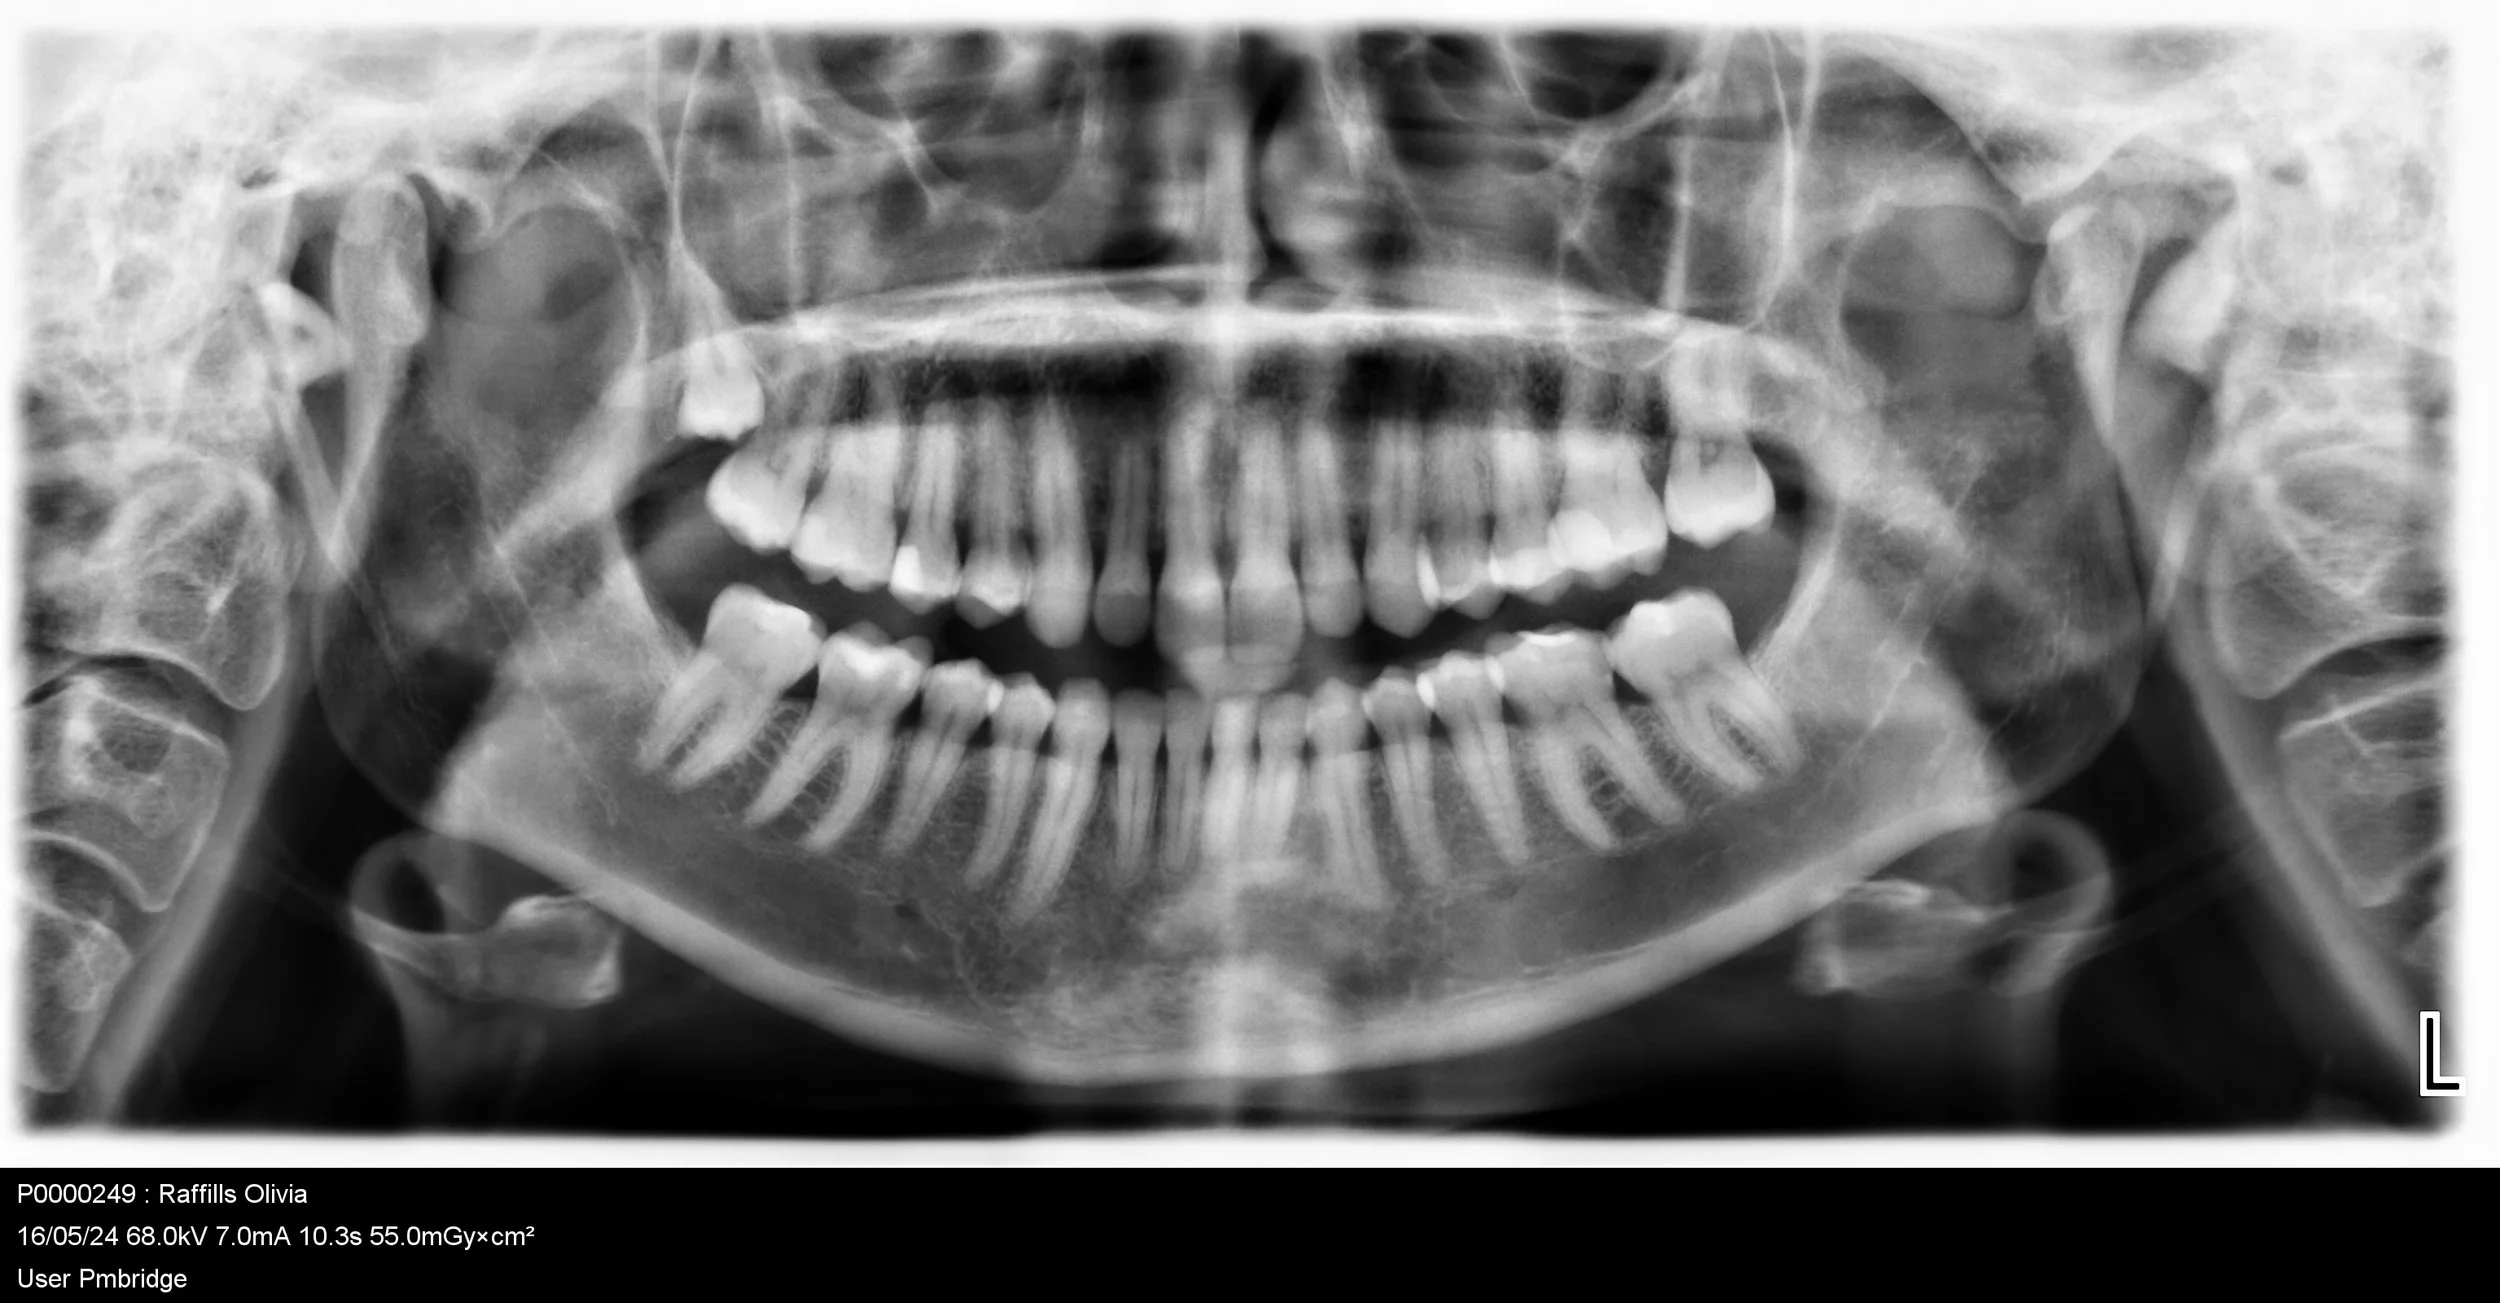

An OPG, also known as a panoramic X-ray, is a dental X-ray that offers a panoramic view of the teeth, mouth, and jaws.

An OPG, also known as a panoramic X-ray, is a dental X-ray that offers a panoramic view of the teeth, mouth, and jaws. This comfortable and non-invasive test involves the patient biting down on a small piece of plastic while the OPG machine rotates around their head to capture a two-dimensional image from ear to ear. This valuable diagnostic tool helps dentists identify various dental and oral health issues.